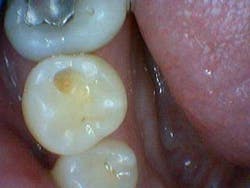

This was the first question out of my patient’s mouth when I diagnosed him with a cavity at his new patient exam. Of course he had to ask … his last filling was when he was 14 (he is now 37), and understandably there was an underlying tone of doubt in his voice. After all, what dentist in his or her right mind would look at tooth No. 29 and say, “That’s a cavity”? (Figs. 1 and 2)

Fig. 1

In dental school, we were taught to rely on a sharp explorer and sharp eyes to diagnose caries. Upon initial examination, I did not consider this to be a cavity. If we can’t see it, it’s not there, right? Why doubt what we were taught? The answer is simple. Because we can’t SEE everything that needs to be diagnosed, we therefore need to utilize adjunct diagnostic tools to be sure we are thorough in our examinations.